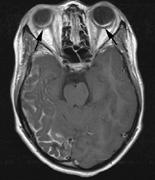

1. Schwannomas most commonly affect the fifth cranial nerve (CN), but any cranial nerve may be affected. In contrast to vestibular schwannomas (CN VIII), these typically do not grow large.84,90 Vestibular schwannomas (acoustic neuromas) are the classic finding in NF2 (Fig. 7). The risk for malignant transformation is low, but may be higher with radiation exposure.84,94

Fig. 7. Neurofibromatosis type 2: Images of a 12-year-old boy with deafness and weakness in his arms and legs, whose father has bilateral deafness. Axial T2-weighted (a) and postcontrast axial (b) T2-weighted images reveal bilateral vestibular schwannomas, which are also known as acoustic neuromas (arrows). This is the classic finding of NF2. (b, c) Bilateral schwannomas are seen in Meckel's cave (arrowheads) and a (d) lower left cranial nerve schwannoma extends into the pars nervosa of the jugular foramen (arrow). (e) A part cystic and part solid enhancing ependymoma in seen within the cervical cord and medulla and within the distal cord and conus. (e, f) Thoracic schwannomas are present at numerous levels (arrowheads). Marked enhancement and thickening of the roots within the cauda equina also represent multiple schwannomas.